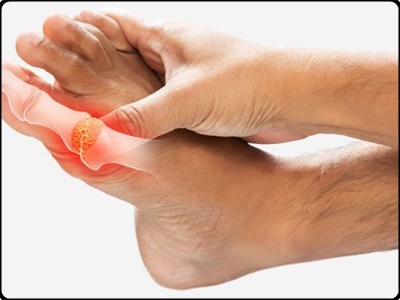

통풍은 체내의 요산이 신장을 통해 정상적으로 걸러지지 못하기 때문에 발생합니다. 이는 몸속에 노폐물이나 독소가 필요 이상으로 축척되어 있는 상태라는 것을 말합니다. 때문에 통풍 증상이 시작되면 염증 부위에 심한 통증을 동반할 뿐만아니라 심하게 부풀어 오르게 되며 통증 부위는 빨갛게 붓고 만질 수 없을 정도의 통증을 호소하게 됩니다.